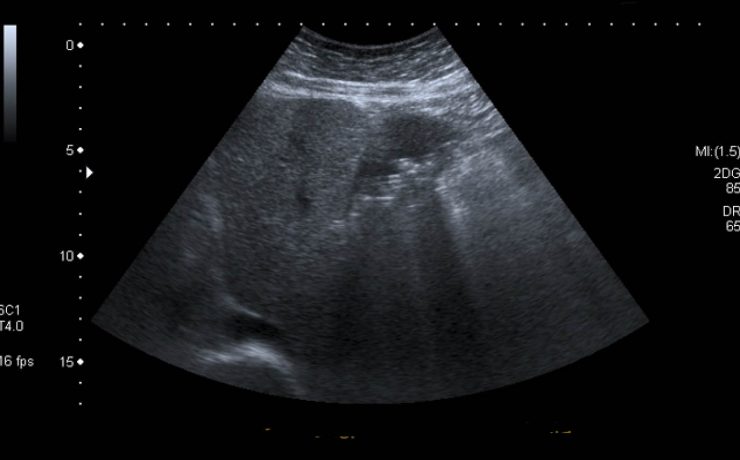

Fibroadenoma de tejido mamario ectópico axilar

Es el tumor benigno más común de la glándula mamaria de mujeres jóvenes. A pesar de que un 95% de las mujeres existe tejido mamario en la axila (cola de mama) y de que incluso en 6 de cada 100 es clínicamente evidente. Los reportes de este tumor en la